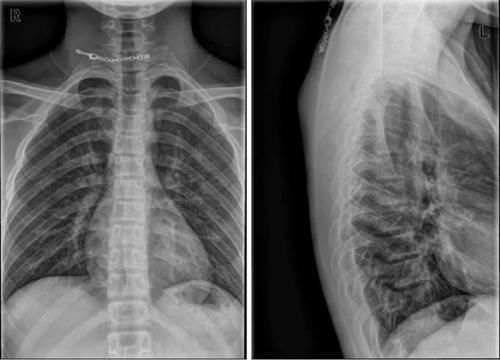

Case12:F,4y;患儿颈部活动受限1个月。

文章插图